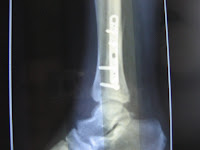

De cand am avut aceasta problema, am cautat pe net un sistem de recuperare, dar nu am gasit si astfel, m-am gandit sa public eu recuperarea pe care am facut-o si care s-a dovedit a fi foarte buna reusind o recuperare de 90% in aproximativ 8 saptamani de la accident.Deci sa incepem: